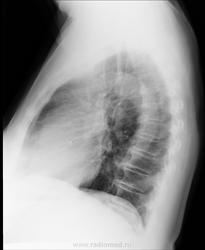

Левый корень не вполне рентгеновская норма, если учитывать, что основу тени корня представляют сосуды. Т.е расширение сосудов, скорее ЛА, может быть вполне.

Да нет, нормальный корень, на мой взгляд.

левый корень б/о

Патологических изменений не нахожу. Не мучила бы ни пациента, ни себя.

Норма

Я не к дообследованию - упаси боже! Я к обьяснению почему так выглядит корень + возраст.